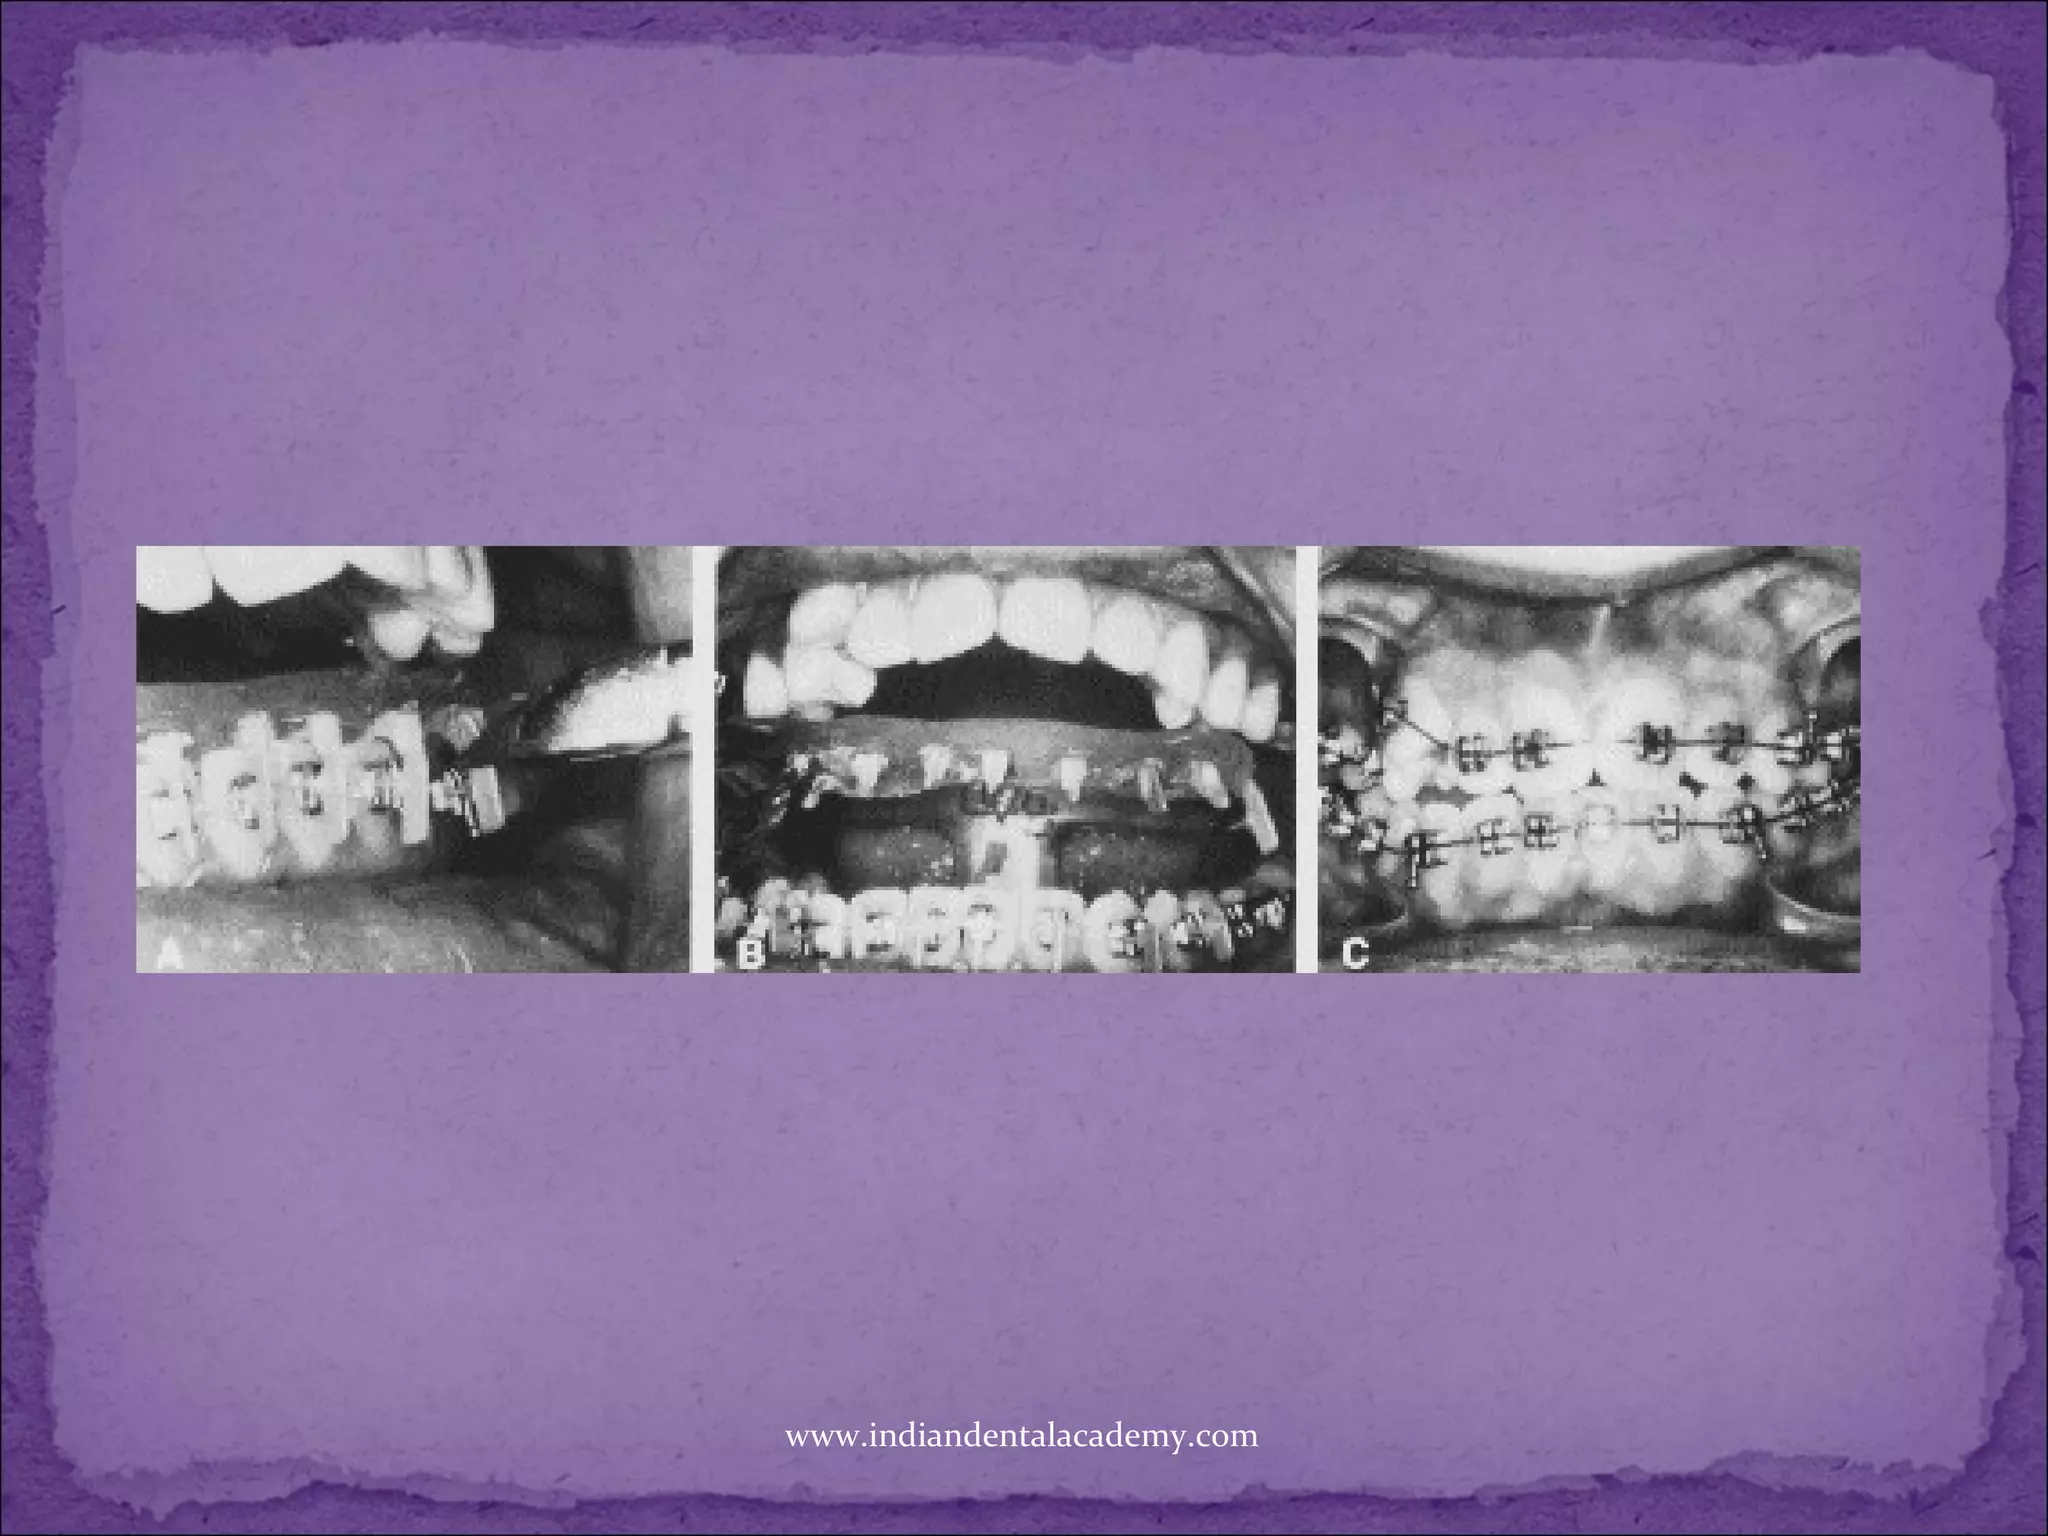

Auto-Tach, This new and important product

eliminates two steps of the previous indirect

technique.

Due to its fluid consistency and adequate working

time, Auto-Tach can be loaded into the Bracket Tray

without undue haste.

After the tray is inserted into the mouth, no

ultraviolet light is needed to set the material, since it

is a thermoset and self polymerizes rapidly in the

warm environs of the oral cavity. In short, the fewer

steps involved, the faster the technique